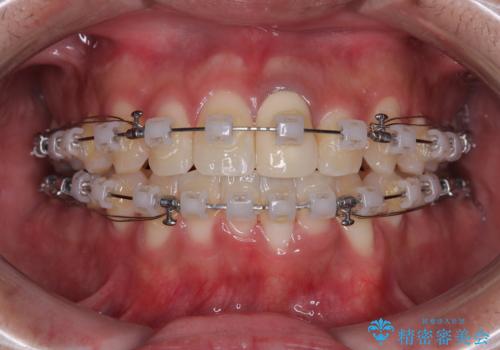

- クリアブラケット

- 治療期間

- 1年10ヶ月